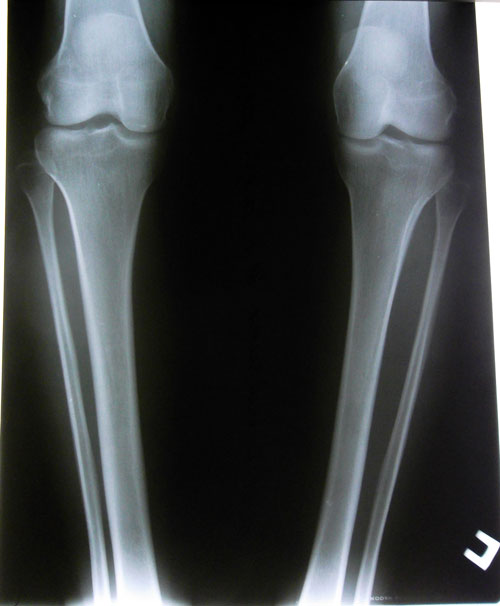

Рентгеновский снимок до операции.Рентген за 3 недели до снятия аппаратов.